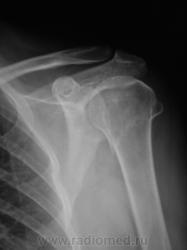

Травма. Пациент направлен на рентгенографию плечевого сустава.

хирургической шейки, вколоченный, с отрывом большого бугра.

Всего бугорка?